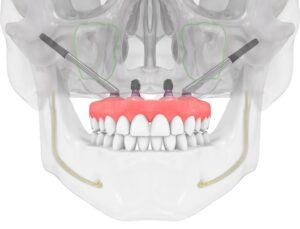

🔹 تقنية All-on-4

4 زرعات تدعم فك كامل

إمكانية التحميل الفوري

مدة علاج أقصر

🔹 تقنية All-on-6

6 زرعات لثبات أعلى

توزيع أفضل لقوى المضغ

مناسبة لفقدان العظم المتوسط

🔹 تقنية All-on-8

أعلى درجات القوة والثبات

أقرب ما يكون للأسنان الطبيعية

مناسبة للمرضى الأصغر سنًا أو ذوي قوة المضغ العالية